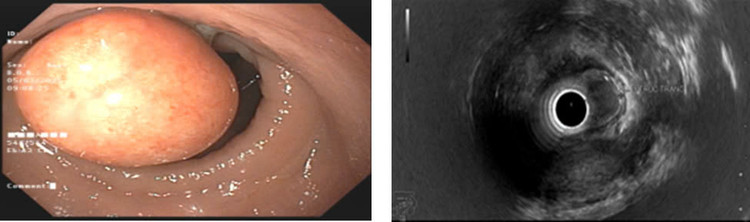

Bệnh nhân được tiến hành nội soi thực quản, dạ dày, đại tràng kiểm tra phát hiện tại trực tràng cách rìa hậu môn 5cm có khối u màu vàng nhạt, đường kính khoảng 18mm, bề mặt nhẵn, niêm mạc phủ giống niêm mạc xung quanh và được chẩn đoán theo dõi u dưới niêm mạc trực tràng.

Ngay sau đó các bác sĩ Khoa Nội tiêu hóa tiến hành siêu âm nội (EUS) để đánh giá xác định bản chất, mức độ xâm lấn của khối u. Trên hình ảnh siêu âm nội soi thấy tổn thương tương ứng với khối giảm âm đồng nhất kích thước 16x18mm, nằm ở lớp thứ 2, 3 của thành trực tràng, hạch xung quanh không quan sát thấy. Các bác sĩ kết luận đây là khối u thành trực tràng theo dõi u cơ chưa loại trừ u Carcinoid hoặc GIST.

| Hình ảnh khối u trên nội soi ánh sáng trắng và siêu âm nội soi - Ảnh BVCC |